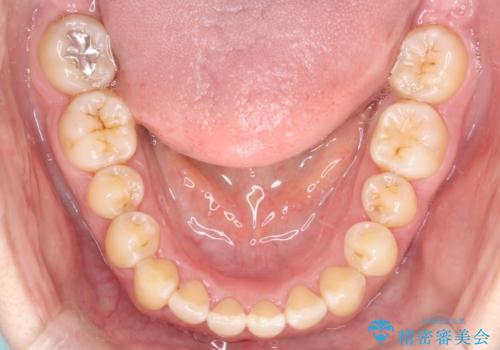

【インビザライン】前歯のすきまを閉じたい

- 前歯の隙間を主訴に来院されました。

インビザライン にて治療を行い、歯並びを改善することができました。